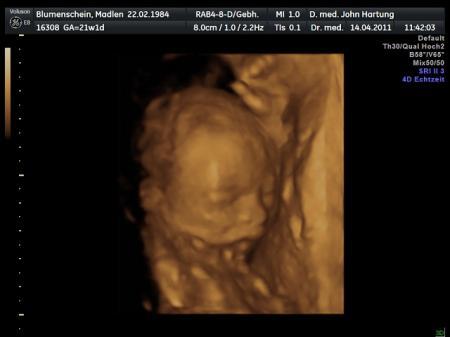

Hallo zusammen. Ich sollte ja ein Mädchen bekommen, was meine FÄ mir ja bei der letzten Untersuchung vorgestern schon mal doch als Jungen ausgewiesen hat. Heute dann die Bestätigung: eindeutig ein Schniepel dran. :-) Er ist gesund und wird gut versorgt, wiegt allerdings erst 316 g und ist etwas kleiner, als normal. Daher muss ich jetzt am 06.05. nochmal zur FD. Dann wird nochmal geprüft, ob er altersgerecht groß ist oder ob der Entbindungstermin verschoben werden muss. Es handelt sich hier zwar nur um 6-7 Tage, aber er will sicher gehen. Naja, was soll´s. Dann eben nochmal 360 km fahren... Was macht man nicht alles... ;-) Kann ich da eigentlich bei der Krankenkasse Fahrgeld oder so beantragen? Ich versuch mal ein Bildchen mit hochzuladen. Bis bald! LG Madlen

Bild zu Zurück von FD... - Forum für August - Mamis

2. Foto

Bild zu